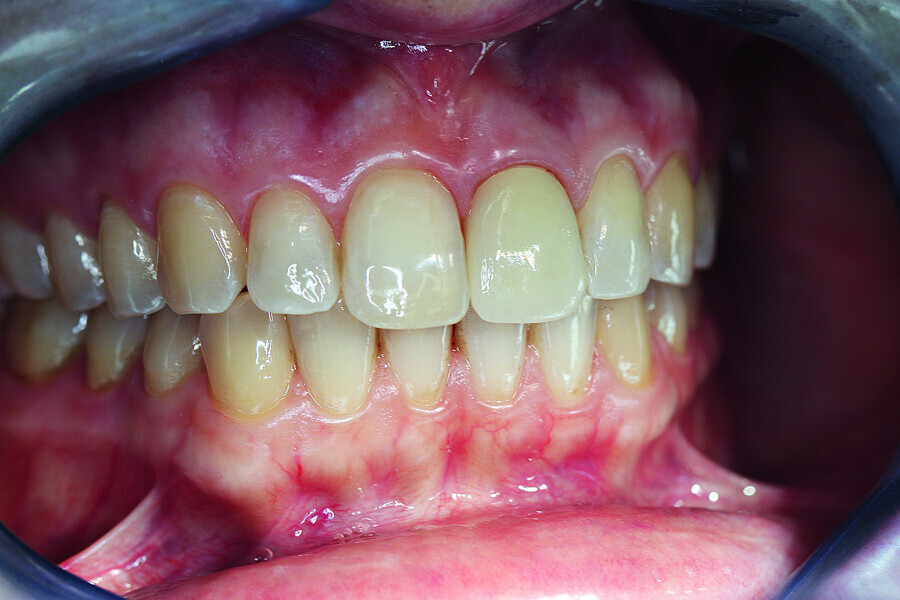

Fig. 18: Final image immediately after inserting the crown with an ideal red–white aesthetic.